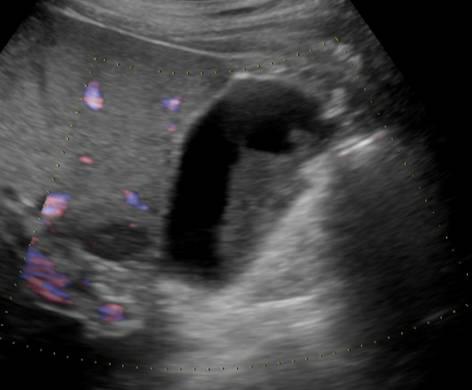

Bùn túi mật

Bùn túi mật - Ảnh 2

» Thông tin: Nam giới – 60 tuổi.

» Lâm sàng: Đau mạn sườn phải.